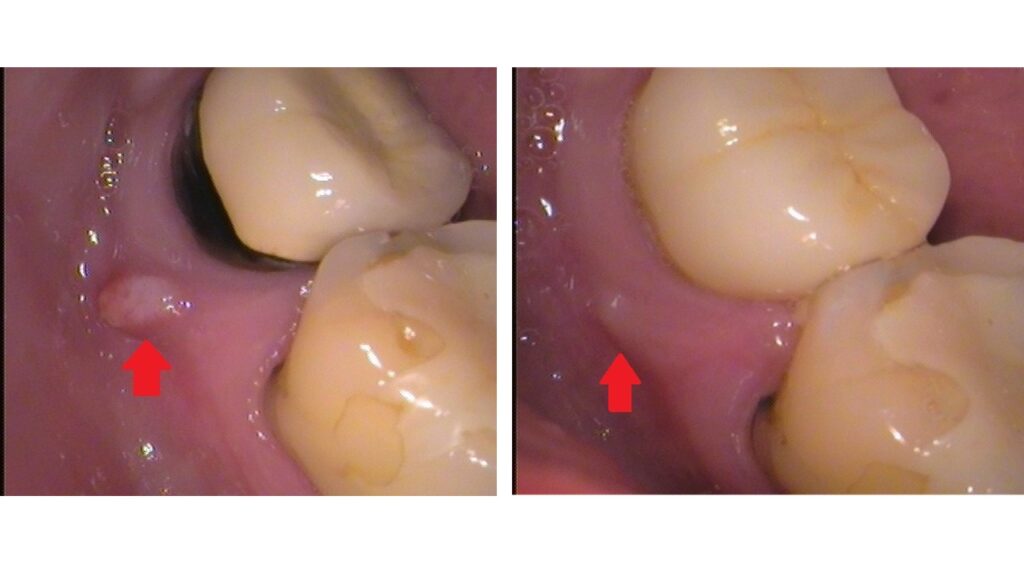

お口の中を見てみると、

歯ぐきにできものがあります。

その場所の歯はセラミックのかぶせ物がされており、以前に神経を抜いた歯です。歯の直下にできた、小さい腫れたできものができた場合、ほとんどが歯の根の先に膿がたまっているのが原因です。

治療2年後の状態です。

その後、特に症状は出ず、全く気にならず生活しているとの事です。

お口の中はセラミックのかぶせ物が入り、

できものは無くなりました。